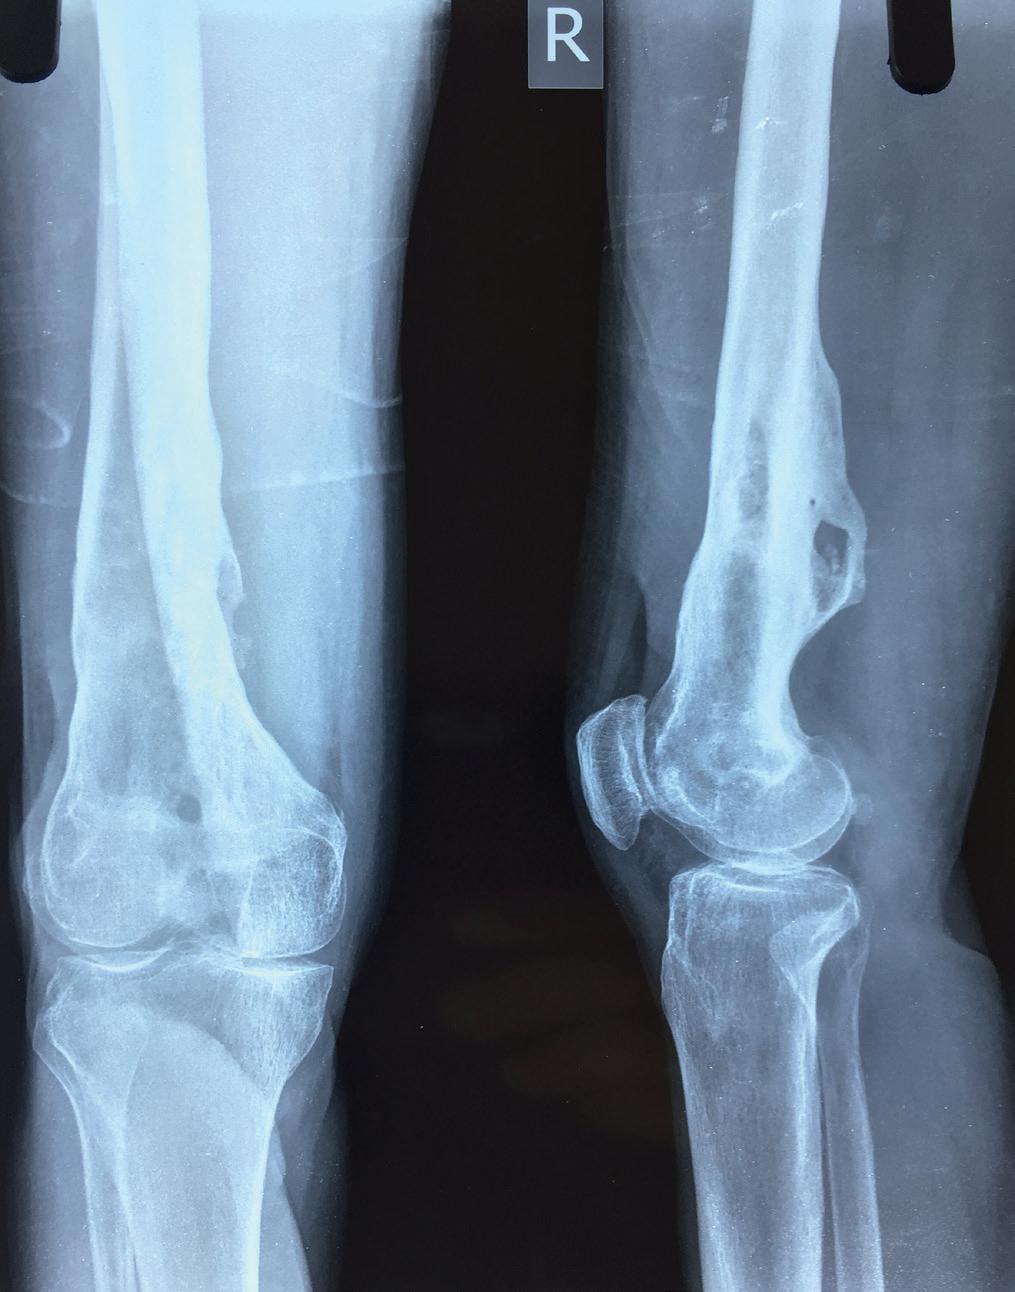

For meg som ortoped var det interessant å se at pasientgruppen som kom med skader ikke var den samme som i Norge. Mens vi i Norge sliter med eldre pasienter med lårhalsbrudd, er det barn med albuenære frakturer som er hovedproblemet i Nepal, og det var en til to slike pasi-

En spesiell pasient har fulgt meg gjennom flere av mine opphold i Nepal. Jeg traff ham første gang i 2018. Han hadde fått kvestet høyre ben av en stor stein omtrent ti år tidligere. Pasienten ble den gang sendt til Kathmandu for å få behandlet benet sitt. Med lappeplastikk på leggen, delhudstransplantasjoner og margnagling av femur fikk man reddet underekstremiteten, men dessverre satt han igjen med en osteomyelitt i høyre distale femur (Bilde 2). Han ble reoperert flere ganger i ettertid, men til ingen nytte. Det var vedvarende sekresjon av illeluktende puss (penicillin-sensitive Staphylococcus aureus) fra dorsalt på låret. Vi, ved sykehuset i Okhaldhunga, reviderte benet hans på nytt med en lokal sekvestrektomi (fjerning av dødt benvev - sekvester) og S53P4 bioaktive glass- implantasjon (4,5). Dessverre hjalp dette bare i noen måneder. Deretter var infeksjonen tilbake igjen. Om alkoholproblemet hans kom før eller etter ulykken vet jeg ikke, men det hjalp heller ikke med tanke på etterlevelse av instruksjonene han fikk.

behandling Pasienten innfant seg ikke med dette og oppsøkte derfor på nytt sykehuset i Okhaldhunga i 2022 for en ”second opinion”. Det var da jeg traff ham for andre gang. Vi fant at pasienten hadde to fistelganger, den ene secernerende, og på nytt et sekvester dorsalt i distale femur. Pasienten fikk beskjed om at vi ville gi ham en siste sjanse. Det kunne bli en stor operasjon under to betingelser: Han måtte ta antibiotika tablettene sine etter operasjonen og dersom det ble et problem i forløpet måtte vi få lov å amputere benet. Det sa han ja til. Noen dager senere var vi i gang med operasjonen – via lateral subvastus tilgang til dorsale distale femur ble det utført saucerisasjon (fjerning av kortikalt ben og sekundær bentilheling) av hele bakre distale femur sirkumferens, margboring mot proksimalt og kyrettasje, i tillegg til margboring mot distalt (6). Heldigvis hadde jeg med meg en meget flink nepali kirurg som gjorde en møysommelig eksisjon av begge fistelgangene (Bilde 3). Vi la bølgedren i sårhulene og gjorde primær lukking. Pasienten fikk postoperativt kloksacillin i.v. 2 g x 4 i to uker, deretter dikloksacillin 1 g x 4 i fire uker (7). Han ble også instruert i å avstå fra vektbæring på høyre ben i rundt seks måneder, samt at han måtte bruke en stabiliserende kneortose for å forhindre fraktur av en tydelig svekket rørknokkel.

I fjor var jeg tilbake i Okhaldhunga og etterlyste pasienten (Bilde 4). Da han fikk høre at jeg var kommet tok han turen til sykehuset, selv om det innebar utgifter til jeep og flere timer reise. Pasienten var blitt infeksjonsfri, smertefri, muligens alkoholfri og kunne til og med gå korte distanser helt uten støtte. Han strålte fra øre til øre (Bilde 5).